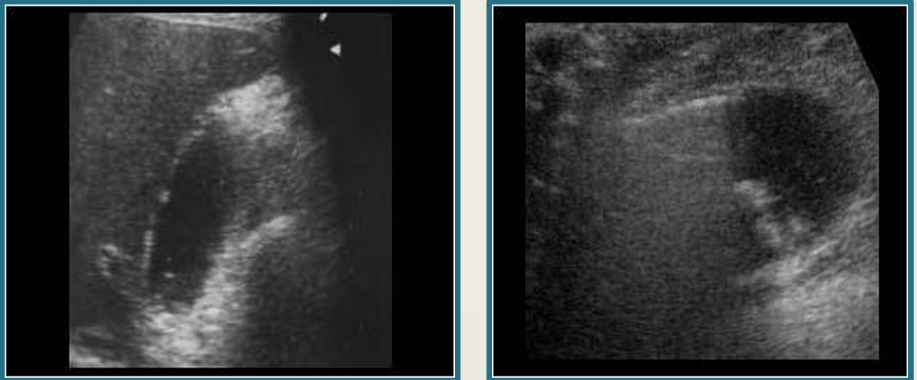

term image

gb polyps

adenomyomatosis